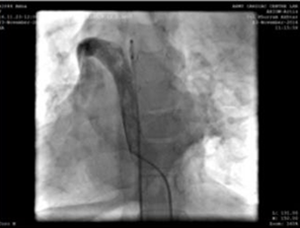

Veine fémorale droite et l'artère ont été canulées gaine radiale 5F utilisé. Au cours de la procédure, nous avons trouvé la veine cave inférieure (IVC) pour drainer à travers la continuation azygeuse dans la veine cave supérieure droite, puis suivre à travers le sinus coronaire dilaté dans l'oreillette droite. Une décision pour effectuer la procédure de la veine jugulaire interne gauche (accessible avec la gaine radiale 5F) a été prise.

Ponction de la veine jugulaire gauche et cathéter d'angiographie 5F, montrant la veine du bras supérieur-veine cave supérieure-chemin de connexion de l'oreillette droite.

Nous avons utilisé une gaine de livraison 9F, qui a été avancée et placée dans l'aorte descendante sur le fil de guidage super-rigide. Une MemoPartTM cone shape PDA occluder 14/12 mm, was attached to the delivery cable and progressed across the delivery sheath. The placement of the occlude was proper with no residual flow.